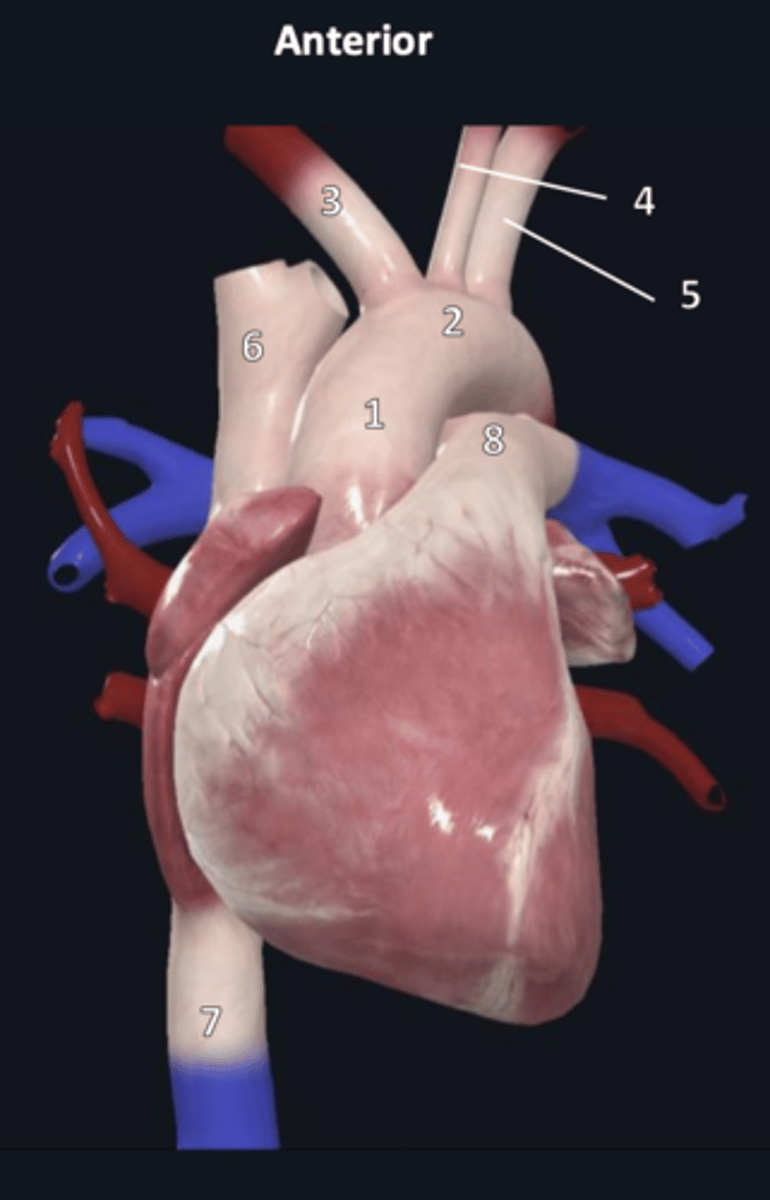

ascending aorta

1

aortic arch

2

brachiocephalic trunk

3

left common carotid artery

4

left subclavian artery

5

superior vena cava

6

inferior vena cava

7

pulmonary trunk

8